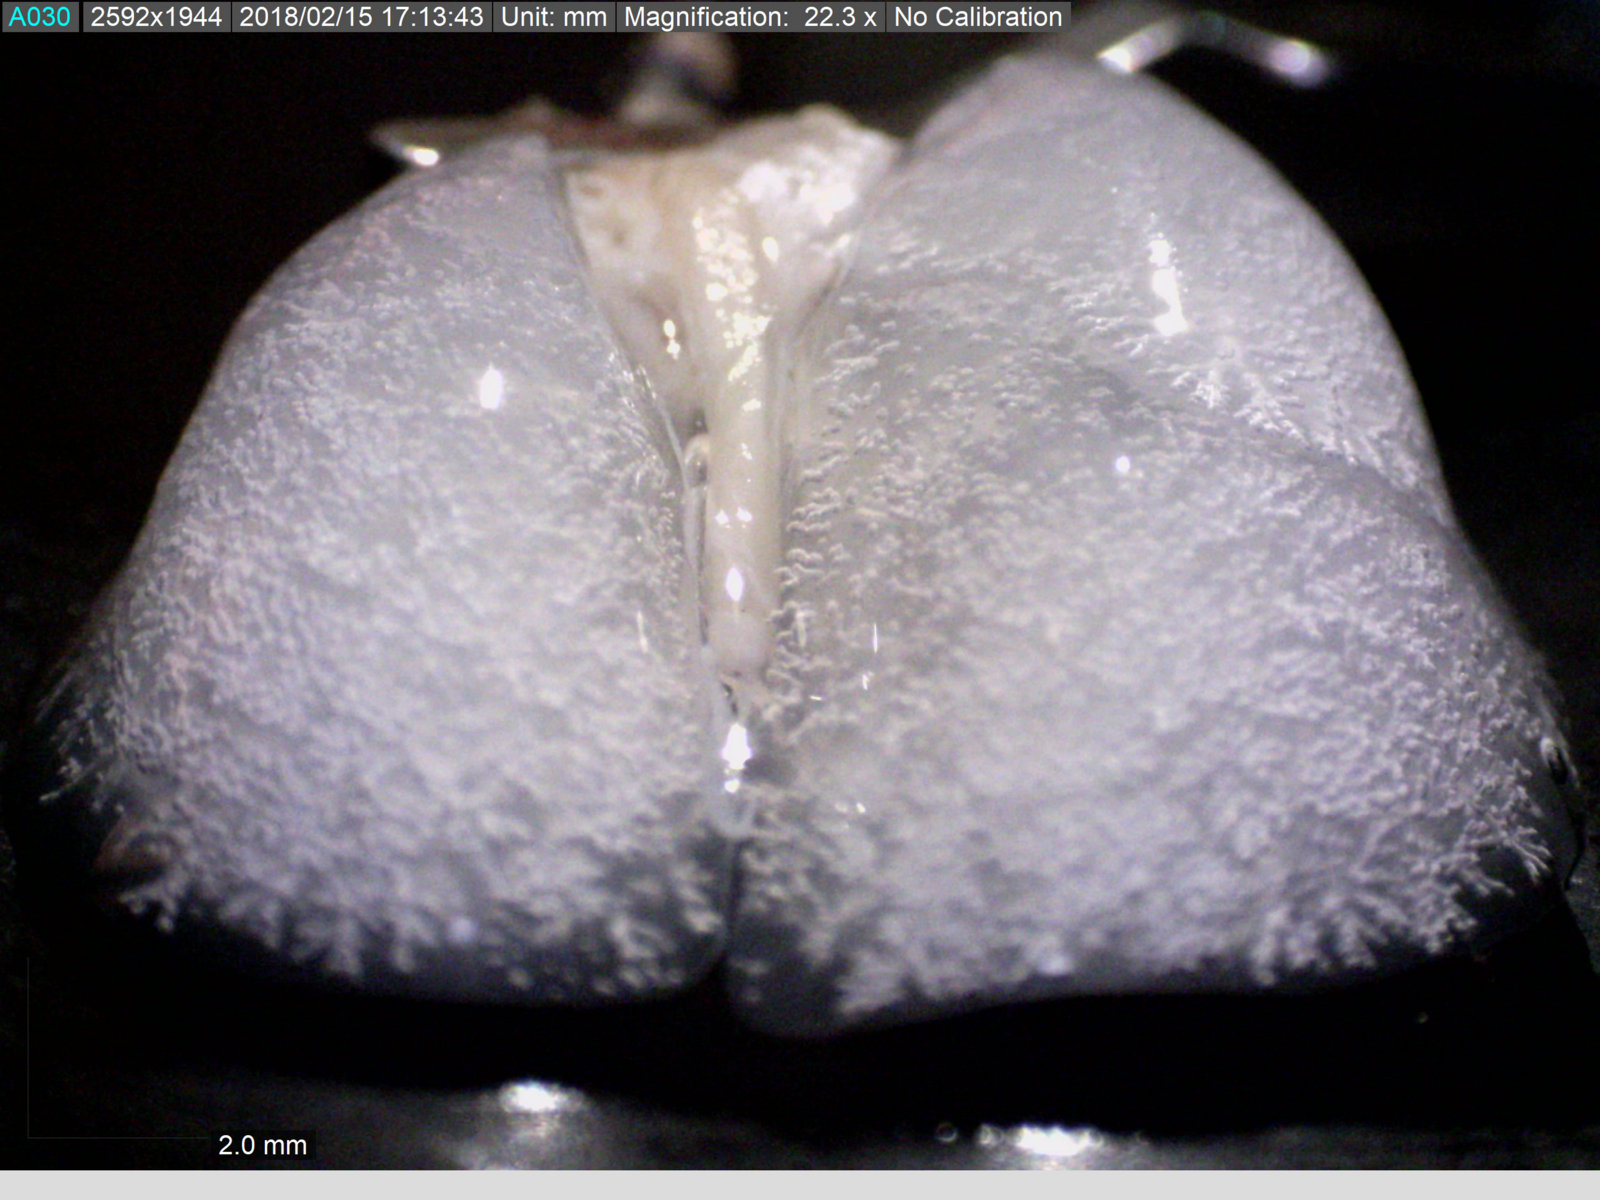

Fare akciğerinde operasyon sırasında mikroskoptan görüntü

"Gerçek hayatta ise bu ajanların vücuda girer girmez vücuttaki savunma mekanizmalarına karşı koyup tümör dokusuna ulaşmaları gerekiyor" diyen Dr. Bölükbaş, sözlerini şöyle sürdürdü:

Biz çalışmalarımızda, fare boyutunda da olsa, bunu göz önünde bulundurarak gerçeğe en yakın modelleri tercih ediyoruz. Birçok nano ajan kan yoluyla enjekte edildiğinde hedefi başka bir organ olsa bile özelliklerine göre ya vücuttan atılıyor ya da toksik madde olarak algılanıp karaciğerde kendini buluyor. Kendi tasarımımızın da önce bu problemle karşılaştığını gösterdikten sonra bunun üstesinden gelmek için nanoparçacıklarımızı akciğere lokal yoldan enjekte etmeyi ve akciğer kan dolaşımını bu süreçte izole etmeyi denedik.